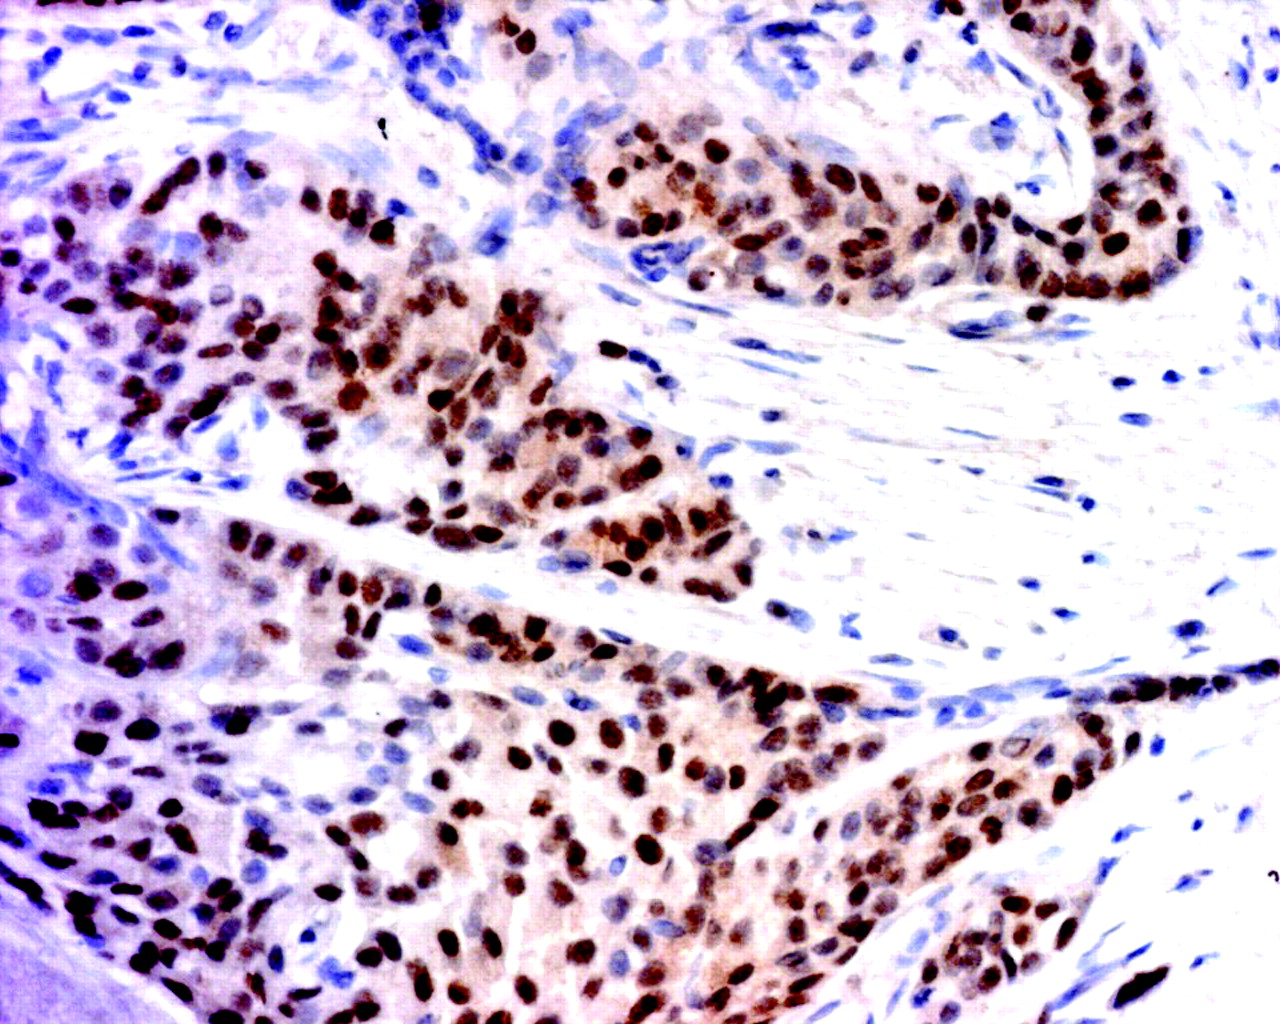

ERα expression. ERα is expressed in about 70% of breast cancer, but, as illustrated above, in ERα -positive breast cancers, there are many ERα -negative cells mixed in with the ERα -positive (brown stain) cells. This image is an example of an invasive ductal cancer of the breast stained with ERα -specific antibody 1D5 (Dako). Cells are counterstained with hematoxylin.